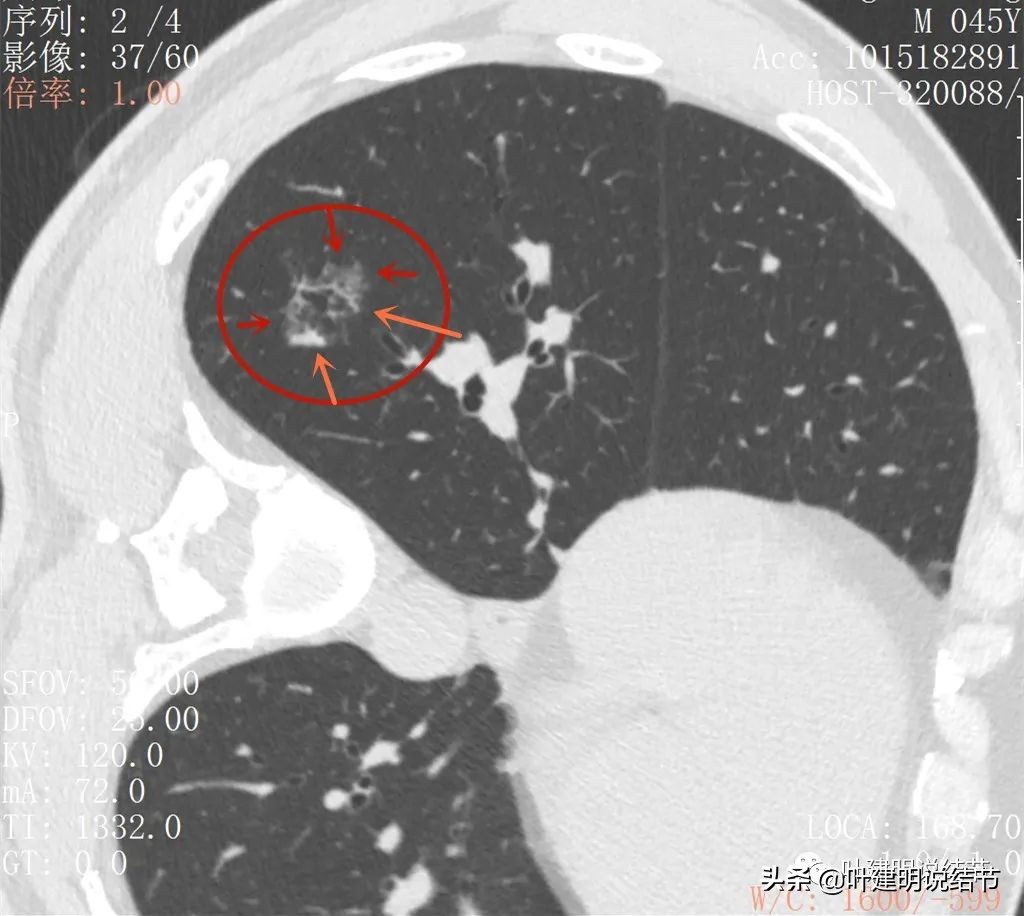

2022年2月平扫:

右下叶淡而散在的磨玻璃影

整体轮廓有点清楚,似见血管走行于病灶处

密度略不均